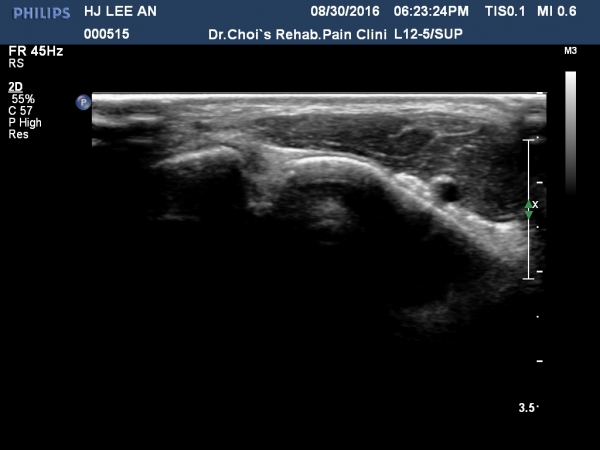

ÃÊÀ½ÆÄ °Ë»ç

¹ß¸ñ ¾ÕÂÊ Á¾´Ü¸é°Ë»ç¿¡¼­ °üÀý³» ¼ö¾×Àú·ù´Â ¶Ñ·ÈÇÏÁö ¾ÊÀ¸³ª °æ°ñ °Å°ñ Á¢Ã˺ο¡ ¼Ò·®ÀÇ

¼ö¾×Àú·ù°¡ °üÂûµÊ(»çÁø 1, 2).